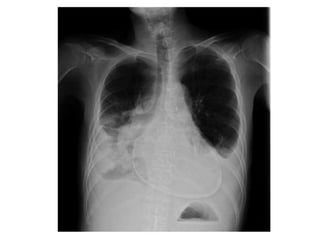

• Pericardial effusion------------

tampnade